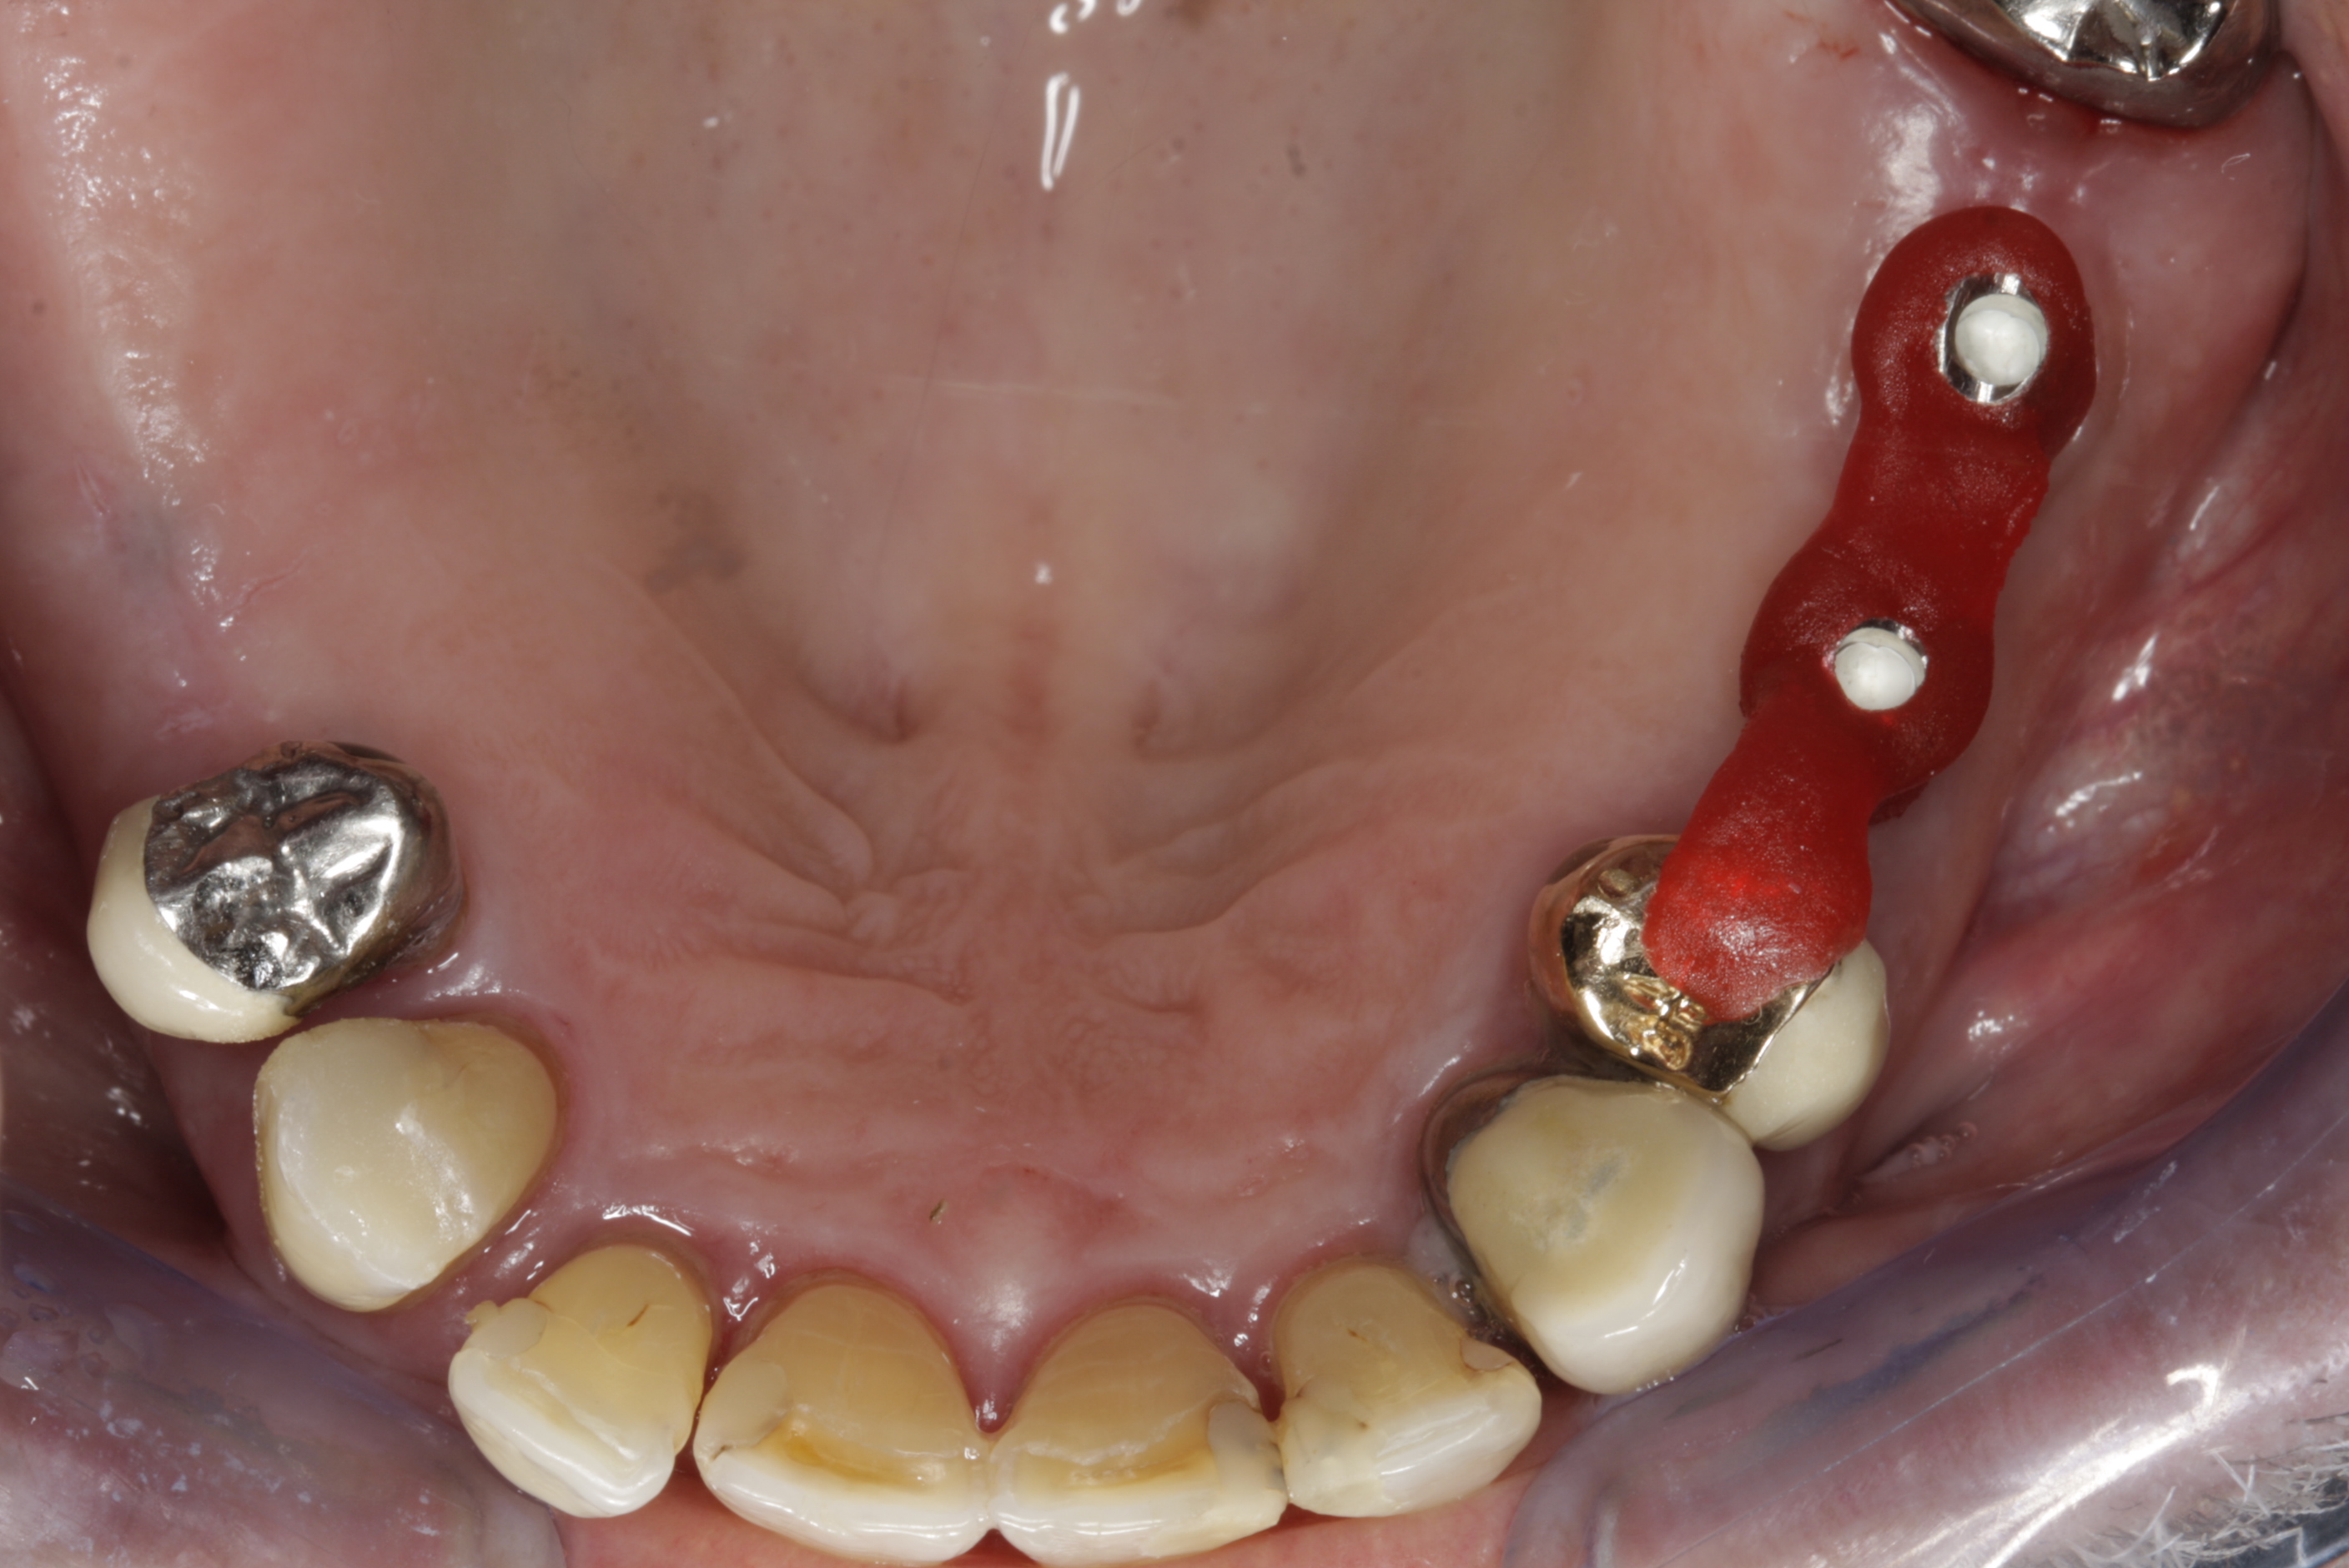

Protetické řešení může být pomocí můstku, který je kotvený na implantátech nebo pomocí jednotlivých korunek na implantátech.

V zásadě je možné do těchto můstků zařadit i přirozené zuby, zejména pokud je potřeba tyto zuby ošetřit proteticky – korunkami. Korunky nebo můstky mohou být na implantáty nacementovány nebo přišroubovány.

Zdravé zuby zůstanou zachovány a přitom náhrady jsou pevné, jako na vlastních zubech